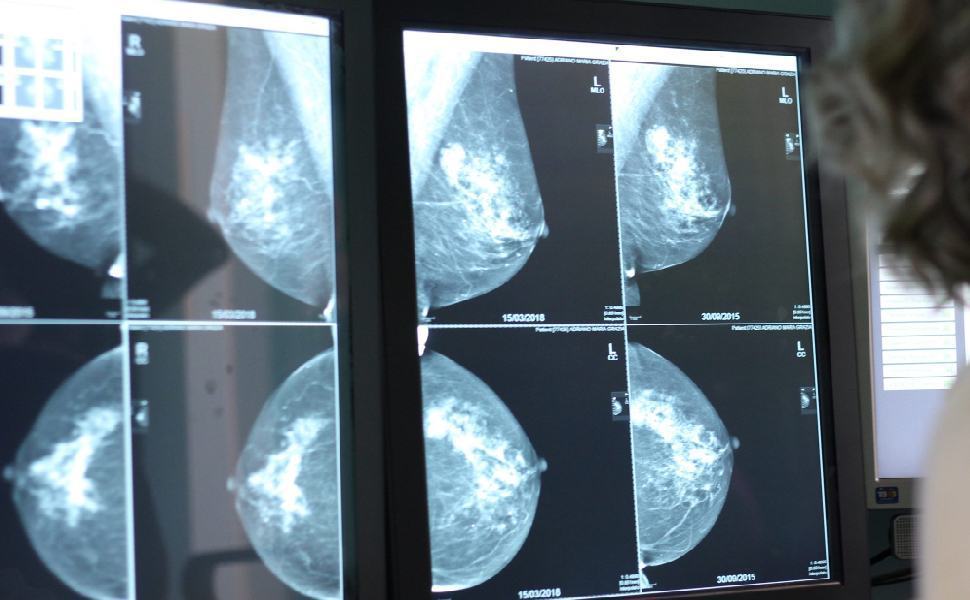

COSENZA – Per anni la Calabria è rimasta in coda alle classifiche nazionali sullo screening oncologico. Nel 2023 i dati collocavano la Regione e in particolare l’ASP di Cosenza agli ultimi posti per adesione alle campagne di prevenzione. Una fotografia amara, che certificava un ritardo cronico, frutto di carenze organizzative, di limiti strutturali e, spesso, di scarsa informazione tra i cittadini. Nel 2025, l’Asp di Cosenza ha avviato un percorso di recupero con un progetto pilota nel distretto Esaro-Pollino. Al centro dell’esperimento, un’alleanza concreta con i medici di medicina generale, protagonisti nella sensibilizzazione e nella presa in carico delle donne in età utile per lo screening mammografico. Le percentuali di adesione hanno superato il 75-80% partecipazione, cioè livelli mai raggiunti prima in Calabria e persino superiori alle medie attese a livello nazionale.

Il modello Esaro-Pollino ha mostrato che il problema non era soltanto l’offerta di screening, ma la modalità con cui veniva proposto. Le pazienti, spesso diffidenti o poco informate, tendevano a rimandare. A contare, dunque, non era solo la disponibilità di mammografi o di strutture, ma la capacità di instaurare un rapporto diretto, fidato, personalizzato. Qui è entrata in gioco la figura del medico di medicina generale e della sua modello organizzativo digitale, unico interlocutore sanitario quotidiano di gran parte delle famiglie. Grazie al supporto offerto al medico dalla piattaforma digitale di AFT nella stratificazione preliminare di eleggibilità, il contatto diretto, le chiamate, gli inviti personalizzati, la spiegazione chiara dei benefici, è stato possibile abbattere resistenze e paure e semplificare la prenotazione dei medici nelle agende predisposte sulla loro piattaforma di AFT. Un’azione capillare che ha portato a un aumento significativo della domanda di screening, subito tradotto in numeri grazie a una rete di mammografi potenziata con fondi PNRR. L’ASP ha sfruttato i finanziamenti del Piano Nazionale di Ripresa e Resilienza per ammodernare i macchinari. «Abbiamo sostituito i vecchi mammografi con apparecchi di ultima generazione – spiega Rizzo –. Oggi abbiamo dieci mammografi, distribuiti su più presidi. L’innovazione tecnologica, unita alla diffusione territoriale dei punti di accesso, ha ridotto le disuguaglianze tra chi vive in città e chi abita nei paesi montani o nelle aree interne.